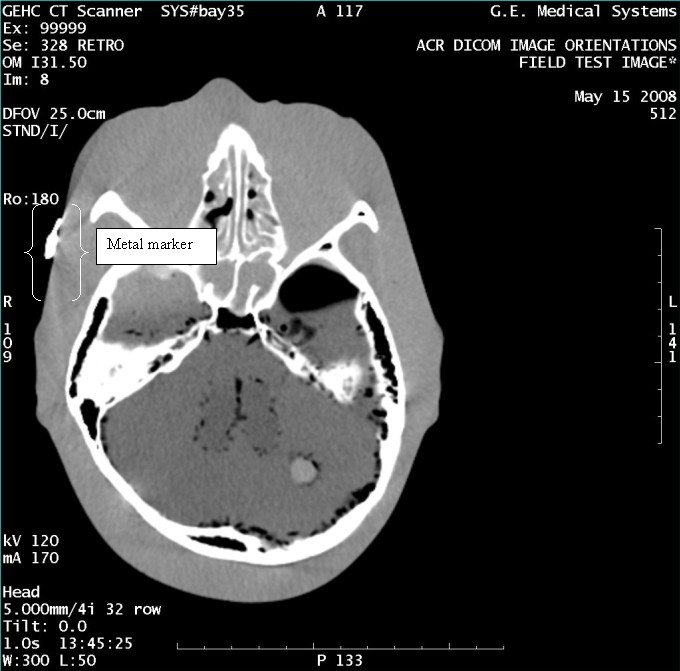

- With the support of the site personnel, examine the images sent

to the Review Station (i.e., 12 series, each with 1 image) and compare

their orientation to the images in this document.

- Each image contains a metal marker on the phantom's right cheek.

- Each image in this document contains a description of the expected

orientation of the metal marker (i.e. to prove Left and Right) as

well as the Posterior and Anterior orientation description.note:

The sample images included in this document use “R”, “L”, “P”, and “A” for “Right”, “Left”, “Posterior” and “Anterior” orientation. The Hospital Review Station may use a different style of annotation. The style used is not relevant to this procedure.

- Each image in this document has sufficient space to store the observed results for up to 4 Review Stations.

- Enter ‘Y’ in the space to indicate the observed result matches the expected.

- Enter ‘N’ in the space to indicate the observed result does not match the expected.

- Enter “NA” in the space if a column is not being used.

- Repeat for each destination.

Figure 7. Exam 99999, Series 328

Figure 8. Exam 99999, Series 330